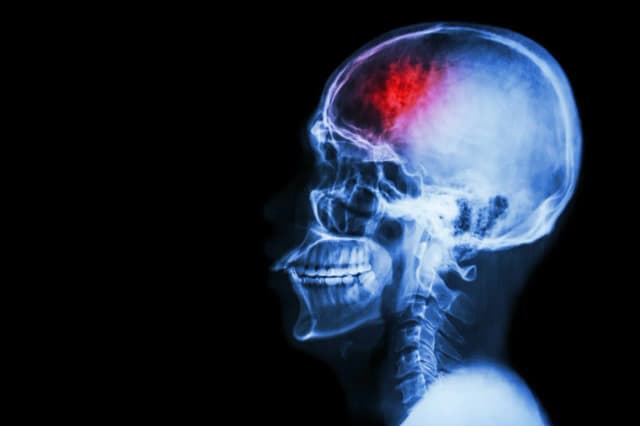

Hospitalizacja po udarze mózgu to kluczowy etap w procesie leczenia, który ma na celu stabilizację stanu pacjenta oraz wdrożenie rehabilitacji. Czas trwania hospitalizacji zazwyczaj wynosi od 1 do 3 tygodni, ale może się różnić w zależności od rodzaju udaru oraz stanu zdrowia pacjenta. W przypadku udarów krwotocznych hospitalizacja może być dłuższa z powodu ryzyka powikłań. Wczesne rozpoczęcie rehabilitacji jest niezwykle ważne, ponieważ przyspiesza powrót do zdrowia i poprawia efekty terapeutyczne. W artykule omówimy, jak długo trwa hospitalizacja, jakie czynniki na nią wpływają oraz jakie są etapy rehabilitacji po udarze mózgu. Kluczowe wnioski

Hospitalizacja po udarze mózgu to moment, który może wywołać wiele pytań i obaw. Ile trwa hospitalizacja po udarze? Zazwyczaj czas hospitalizacji wynosi od 1 do 3 tygodni, w zależności od różnych czynników, takich jak rodzaj udaru oraz stan zdrowia pacjenta. W poniższej tabeli przedstawiamy przykładowe czasy hospitalizacji w zależności od typu udaru.| Rodzaj udaru | Średni czas hospitalizacji |

| Udar niedokrwienny | 1-2 tygodnie |

| Udar krwotoczny | 2-3 tygodnie |

Udar niedokrwienny jest najczęstszym rodzajem udarów, który oprócz tego, że jest mniej groźny, zazwyczaj prowadzi do krótszej hospitalizacji. Średni czas hospitalizacji wynosi od 1 do 2 tygodni, gdyż pacjent często szybko odzyskuje sprawność. Jednak długość pobytu w szpitalu zależy od stanu zdrowia pacjenta oraz innych czynników, takich jak wiek czy wcześniejsze schorzenia. Osoby w lepszej kondycji fizycznej mogą wrócić do zdrowia szybciej. Z drugiej strony, pacjenci z dodatkowymi schorzeniami, takimi jak choroby serca czy nadciśnienie, mogą wymagać dłuższego czasu hospitalizacji. Dlatego tak ważne jest indywidualne podejście do każdego przypadku.Czytaj więcej: Udar mózgu: objawy, skutki i dlaczego szybka pomoc jest kluczowa

Jak długo trwa hospitalizacja przy udarze krwotocznym? Zrozumienie ryzyka i przebiegu

Udar krwotoczny to poważniejsze schorzenie, znacznie często wymagające dłuższego pobytu w szpitalu. Czas hospitalizacji może wynosić od 2 do 3 tygodni, a czasem nawet dłużej, w zależności od komplikacji, jakie mogą wystąpić. Pacjent musi być monitorowany, aby uniknąć poważnych powikłań, takich jak krwawienie wewnętrzne.W przypadku udarów krwotocznych istotne jest, aby lekarze szybko ocenili sytuację pacjenta. Im szybciej zareagują, tym większa szansa na minimalizację skutków udaru. Z tego powodu czas hospitalizacji może być różny w każdym przypadku.

Hospitalizacja po udarze mózgu jest procesem, który może trwać od 1 do 3 tygodni, a jego długość w dużej mierze zależy od rodzaju udaru oraz stanu zdrowia pacjenta. Ile trwa hospitalizacja po udarze jest istotnym pytaniem, na które warto znać odpowiedzi, aby lepiej przygotować się na ten trudny okres. Udar niedokrwienny zazwyczaj wymaga krótszego pobytu w szpitalu, podczas gdy udar krwotoczny może wydłużyć czas hospitalizacji z uwagi na potencjalne powikłania.